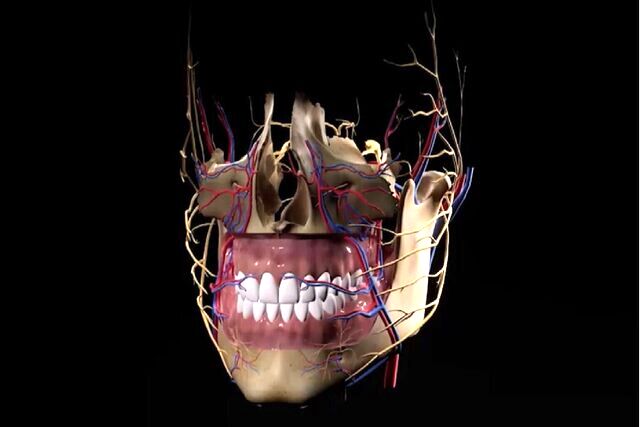

محققان ایرانی موفق شدند با توسعه فناوری چاپ سهبعدی زیستی و تولید ایمپلنتهای جذبشونده استخوانی این نوع ایمپلنتها را در جراحیهای فک، صورت و جمجمه بیماران ایرانی کاربردی کنند و به گفته آنها بازسازی موفق ساختار جمجمه یک خانم که در تصادف، استخوان زیر چشمش آسیب دیده بود از دستاوردهای این گروه در بیمارستان سینا بوده است.

حاجیحسینعلی درباره تفاوت ایمپلنتهای جاذب تولیدی با نمونههای متداول فلزی توضیح داد: در روشهای سنتی، از ایمپلنت تیتانیومی استفاده میشود که باید پس از مدتی طی یک جراحی دیگر خارج شود. اما داربست ما، از مواد زیستی ساخته شده و پس از کاشت، بهتدریج در بدن حل شده و جای خود را به بافت استخوانی طبیعی میدهد. این فرآیند هم کمهزینهتر است و هم برای بیمار راحتتر. این مواد که شامل پلیمرها، هیدروژلها و سرامیکهای زیستسازگار هستند، با ترکیبهایی نزدیک به ساختار معدنی استخوان انسان طراحی شدهاند. برخلاف برخی روشها که از استخوان جسد یا بدن خود فرد استفاده میشود، این داربستها کاملاً سنتزی هستند و خطر انتقال بیماری را نیز به همراه ندارند.

وی کاربرد این فناوری را در بازسازی جمجمه دانست و گفت: در جراحیهای جمجمه، استفاده از تیتانیوم باعث مشکلاتی مثل منع انجام MRI و تحریک اعصاب میشود. اما داربست زیستی ما، بدون این عوارض بهراحتی جای استخوان را میگیرد.

به نقل از ستاد نانو، وی اضافه کرد: نمونههای موفق متعددی نیز ثبت شده است؛ از جمله بازسازی موفق ساختار جمجمه یک خانم که در تصادف، استخوان زیر چشمش آسیب دیده بود. این جراحی در بیمارستان سینا انجام شد و چشم بیمار پس از ترمیم، به موقعیت طبیعی بازگشت.